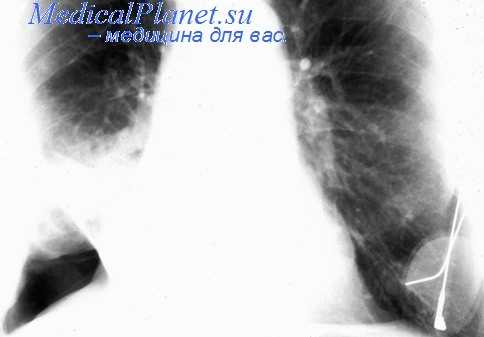

Для первичного выявления осумкованного плеврита чрезвычайно важны данные полипозиционой рентгенографии грудной клетки (в прямой, боковых и косых проекциях) и рентгеноскопии легких. Рентгенологически осумкование проявляется в виде затемнения характерной локализации и формы. В сложных случаях для дифференциальной диагностики требуется наложении искусственного пневмоторакса и пневмоперитонеума, проведение КТ легких. Длительное существование осумкованного плеврита может отразиться на состоянии легочной паренхимы. Поэтому для оценки изменений прилежащих отделов легкого (бронхов, сосудов) используются рентгеноконтрастные исследования - бронхография и ангиопульмонография.

- Рентген. Полипозиционная рентгенография и рентгеноскопия легких при эмпиеме плевры обнаруживают интенсивное затенение. Для уточнения размеров, формы осумкованной эмпиемы плевры, наличия свищей выполняют плеврографию с введением водорастворимого контраста в плевральную полость. Для исключения деструктивных процессов в легких показано проведение КТ, МРТ легких.

Наряду с клиническими проявлениями экссудативного плеврита при осмотре пациента выявляется асимметрия грудной клетки, выбухание межреберных промежутков на соответствующей половине грудной клетки, отставание пораженной стороны при дыхании. Перкуторный звук над экссудатом притуплен, бронхофония и голосовое дрожание ослаблены, дыхание слабое или не выслушивается. Верхняя граница выпота определяется перкуторно, при рентгенографии легких или при помощи УЗИ плевральной полости.